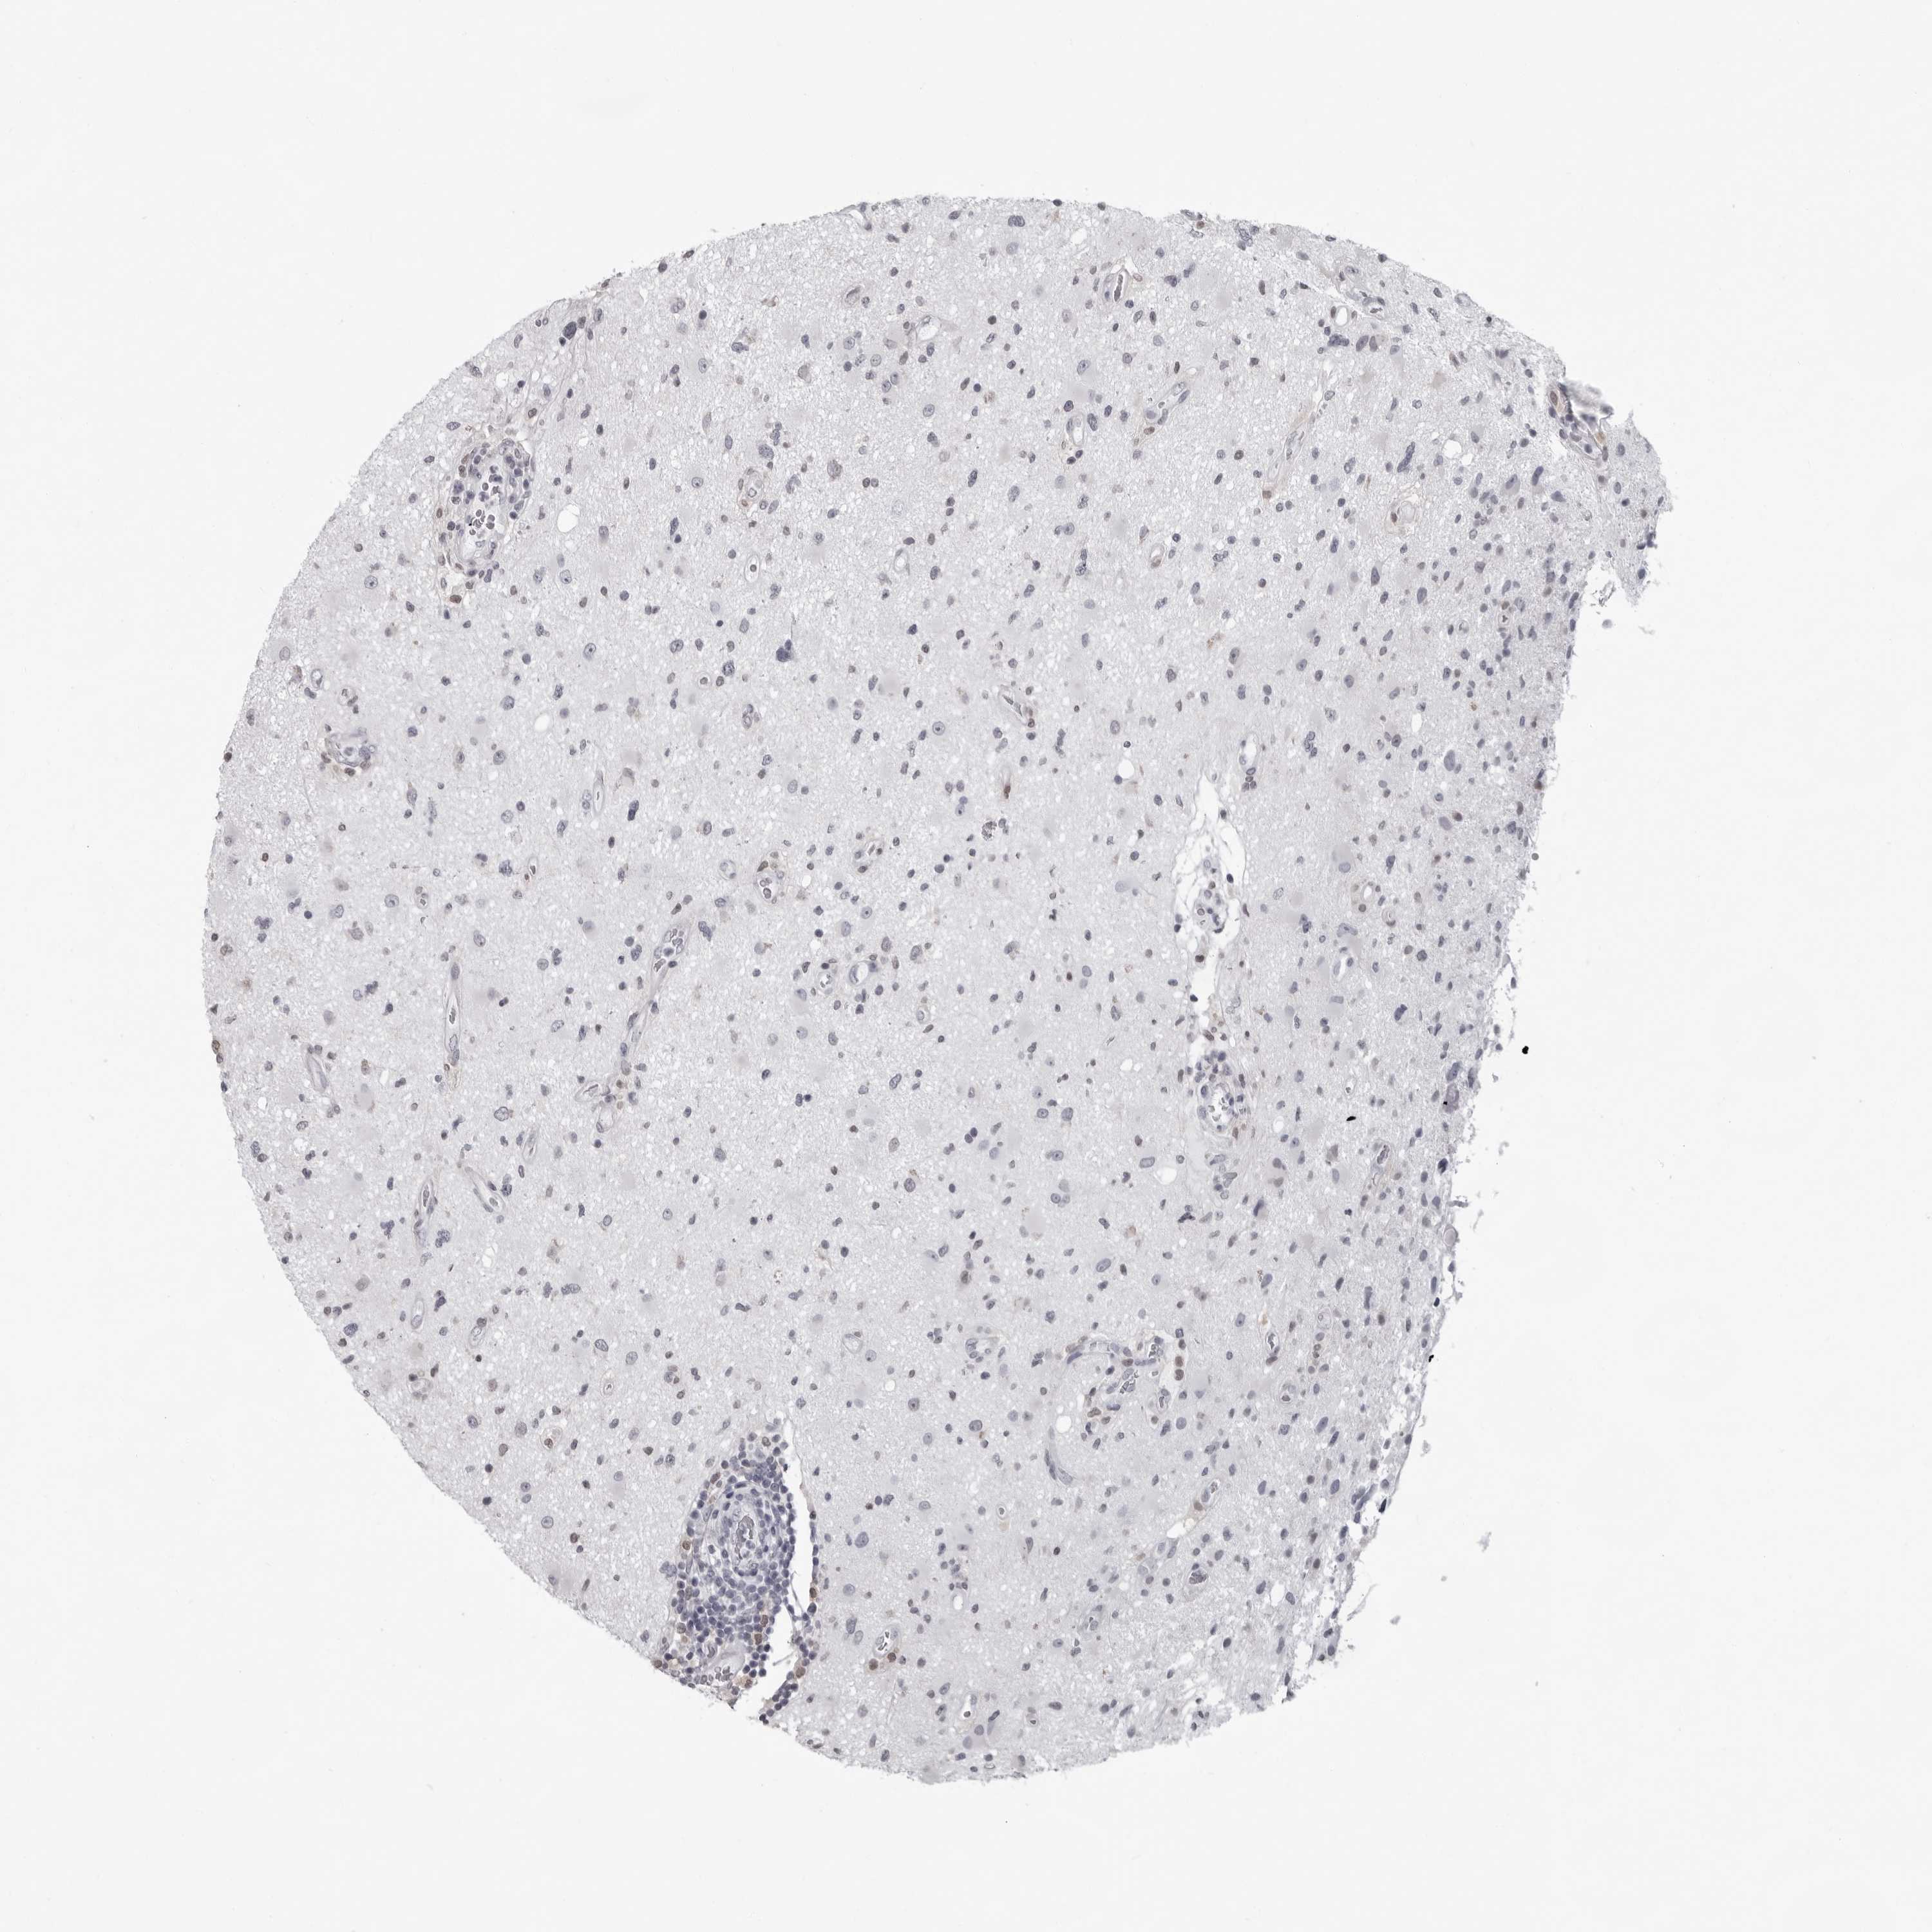

GLIOMA - Protein expressioni

A mouse-over function shows sample information and annotation data. Click on an image to view it in a full screen mode. Samples can be filtered based on level of antibody staining by selecting one or several of the following categories: high, medium, low and not detected. The assay and annotation is described here.

Note that samples used for immunohistochemistry by the Human Protein Atlas do not correspond to samples in the TCGA dataset.

Antibody stainingi

Antibody staining in the annotated cell types in the current human tissue is reported as not detected, low, medium, or high, based on conventional immunohistochemistry profiling in selected tissues. This score is based on the combination of the staining intensity and fraction of stained cells.

Each image is clickable and will lead to virtual microscopy that enables deeper exploration of all samples and also displays staining intensity scores, fraction scores and subcellular localization as well as patient and tissue information for each sample.

Antibody HPA028184

Staining

High

Medium

Low

Not detected

Intensity

Strong

Moderate

Weak

Negative

Quantity

>75%

75%-25%

<25%

None

Location

Nuclear

Cytoplasmic/membranous

Cytoplasmic/membranous,nuclear

Glioma, malignant, High grade

Glioma, malignant, Low grade

Glioblastoma, NOS